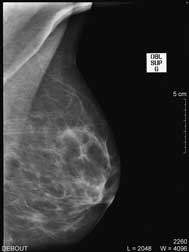

| Debout, le sein légèrement comprimé, deux clichés sont réalisés de face et en oblique sur chaque coté ; d’autres clichés localisés pour mieux analyser une zone peuvent aussi être effectués. |